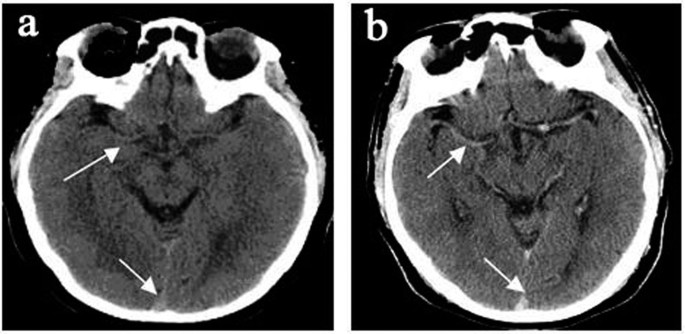

All 45 subjects had brain imaging; of the nine hospitalized patients with encephalopathy eight had CT and one had MRI. CT imaging in the hospitalized group showed diffuse cerebral edema with small ventricles and effaced sulci, as exemplified in Fig. 1. Two of these patients in addition to edema had multiple old cerebral infarcts, and one had chronic thrombosis of the superior sagittal sinus. The brain blood density (CT value of Hounsfield Units, HU) of the bilateral middle cerebral arteries and the superior sagittal sinus was greater in CMS compared to non-CMS groups (Table 1 and Fig. 2). The MRI was obtained in a patient who did not have CT. This 51-year-old female Han Chinese with CMS had resided at 3800 m for 15 years, suffering from headache, dizziness, fatigue, poor appetite, sleepiness, mood changes, and loss of memory for many years. Ten days prior to admission, she developed severe headache, vomiting, irritability, lethargy, and ataxia. Hemoglobin was 24.1 g/dl on admission and 15.4 g/dl after two-month’s treatment that included staying at the lower altitude, as well as oxygen, dexamethasone, and furosemide acutely, followed by Tibetan herbs. CSF pressure was 22.5 mmHg on admission. Initial MRI (Fig. 3) showed markedly increased T2 signal in cerebellar hemispheres, internal capsule, and parietal and occipital lobes that resolved after recovery two months later (Fig. 3). With recovery, apparent diffusion coefficient (ADC) values decreased in the cerebellar hemispheres from 1.26 ± 0.1 to 0.70 ± 0.06 (10−3 mm2/s) (Fig. 3a left& right), and from 0.97 ± 0.07 to 0.75 ± 0.02(10−3mm2/s) (Fig. 3b left & right) in other regions.

(a) Non-CMS subject, 38-year-old male, (b) CMS patient, 46-year-old male, showed higher density of bilateral middle cerebral arteries (arrow) and superior sagittal sinus (arrow), indicating higher blood density.